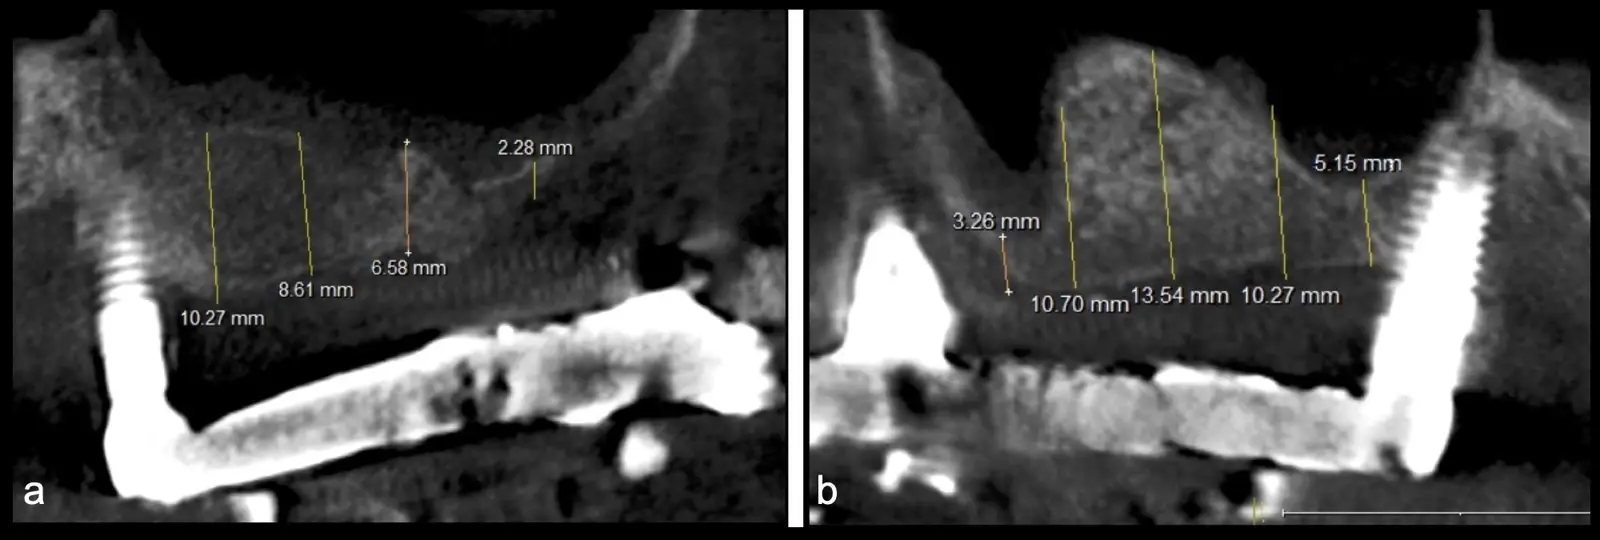

Figura 2. Espesor de la pared lateral (X), altura del reborde residual (Y), profundidad del seno maxilar (Z) y espesor de la membrana sinusal.

Paciente de 62 años, de sexo masculino, llega a la consulta para la colocación de implantes dentales. Refiere haber tenido tratamiento previo con implantes dentales, algunos de los cuales fueron perdidos. A la evaluación clínica se observa ausencia de piezas dentarias en el maxilar superior y 3 implantes remanentes. En la evaluación tomográfica se observa neumatización de los senos maxilares del lado derecho e izquierdo (Figura 14), para lo cual se indica el procedimiento quirúrgico de levantamiento de piso de seno maxilar en ambos cuadrantes, como paso previo a una nueva planificación implantosoportada.

Figura 14. Evaluación intraoral en donde se evidencia presencia de una prótesis híbrida soportada sobre implantes dentales, al retiro de la estructura se observó tornillo protésico fracturado (a, b, c). Evaluación tomográfica: corte sagital a nivel de los senos maxilares derecho e izquierdo, donde se observa una atrofia severa de los rebordes óseos acompañados de neumatización de los senos maxilar (d, f, g).

Figura 31. Control tomográfico post operatorio: corte sagital de ambos senos maxilares. (derecha e izquierda).